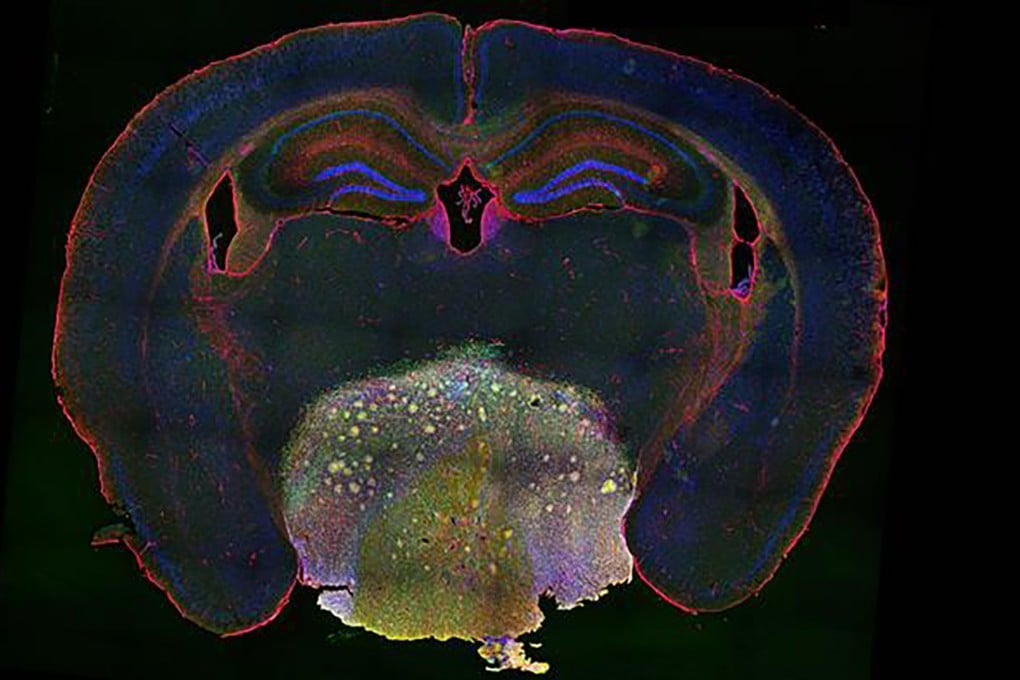

Chinese team finds blood pressure medication shows promise for treating rare brain tumour

Scientists in China say cheap compound might offer relief for craniopharyngioma patients and inform future work on cancer treatments